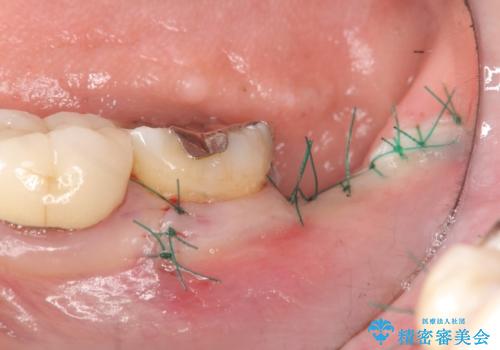

- 左下奥歯の咬合時疼痛を訴えて来院されました。

最後方臼歯周囲には大きな透過像が見られ、破折が強く疑われること抜歯が想定されることを理解していただき銀歯を除去したところ破折が認められたため抜歯を行いました。

今後の機能回復方法としてインプラント治療を希望されたため、将来的に大規模な骨造成が必要とならないよう歯槽堤保存術を抜歯と同時に行いました。